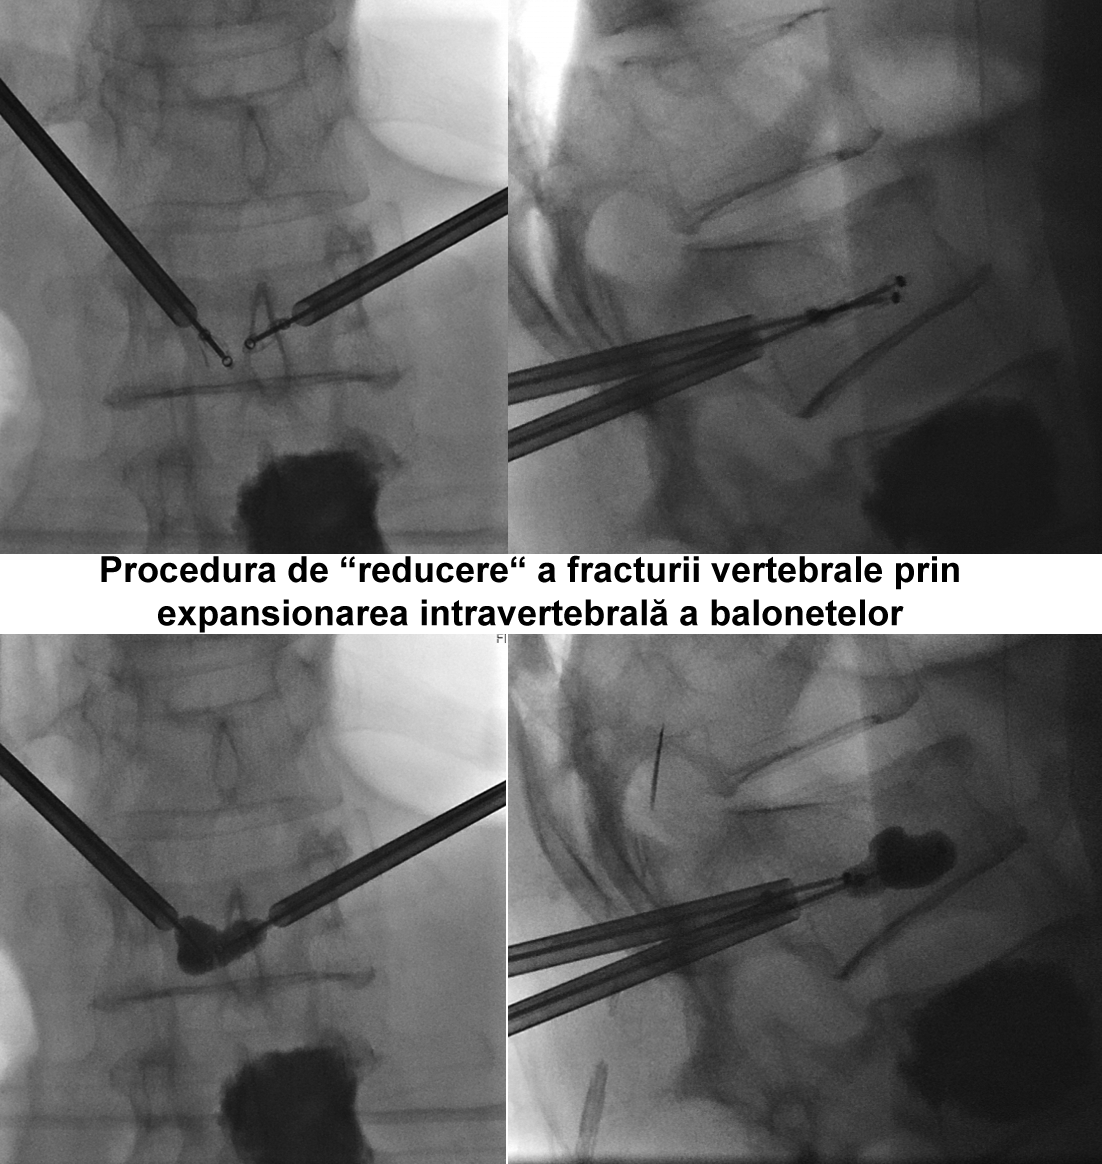

Kyfoplastia reprezintă o procedură minim invazivă în timpul căreia chirurgul introduce în corpul vertebral un tub cu un balon expandabil. Sub control fluoroscopic are loc expansionarea balonului în corpul vertebral, cu restabilirea înălţimii corpului vertebral şi corijarea diformităţii kifotice. Ulterior, în cavitatea formată de balon, se introduce cimentul acrilic, ceea ce contribuie la consolidarea vertebrei.

Realizarea intervenţiilor percutanate de acest tip presupune utilizarea unui fluoroscop intraoperatoriu, cu scopul de a reduce la minim complicaţiile (cum ar fi, leziuni ale structurilor nervoase, scurgerea cimentului extracorporeal, embolii venoase, etc.). În cazul pacientei noastre, a fost utilizată instalaţia de Angiografie tridimensională (3D) Siemens ”Artis Zee”, disponibil în sala de operaţii Hybrid a Spitalului Clinic Republican, care asigură o calitate excepţională a imaginilor intraoperatorii.

- Kyfoplastia cu baloane expandabile a corpului vertebral LI.

Vertebroplastia percutană a corpului LII a fost executată prin abord unilateral transpedicular pe stânga, în timp ce Kyfoplastia cu baloane expandabile a corpului vertebral LI - prin abord bilateral transpedicular pe stânga.